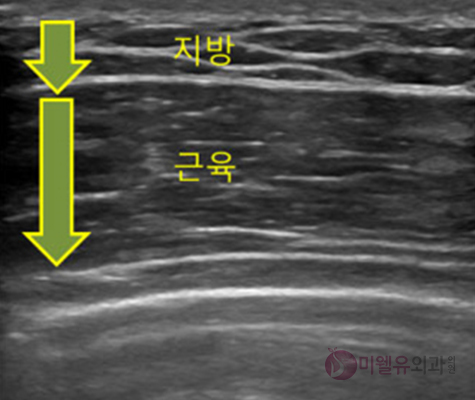

- 수술 전후 초음파에 의한 진단

대부분의 경우 유방조직과 지방조직을 동반한 경우가 많아

유선제거수술과 지방흡입치료가 동시에 필요합니다.

대부분은 지방과 유선조직이 동시에 있는 형태가 많습니다.

그러나 남성유방암 등의 감별을 위해 초음파를 통해 정확한 진단이 필요합니다.

수술 전 검사(초음파)